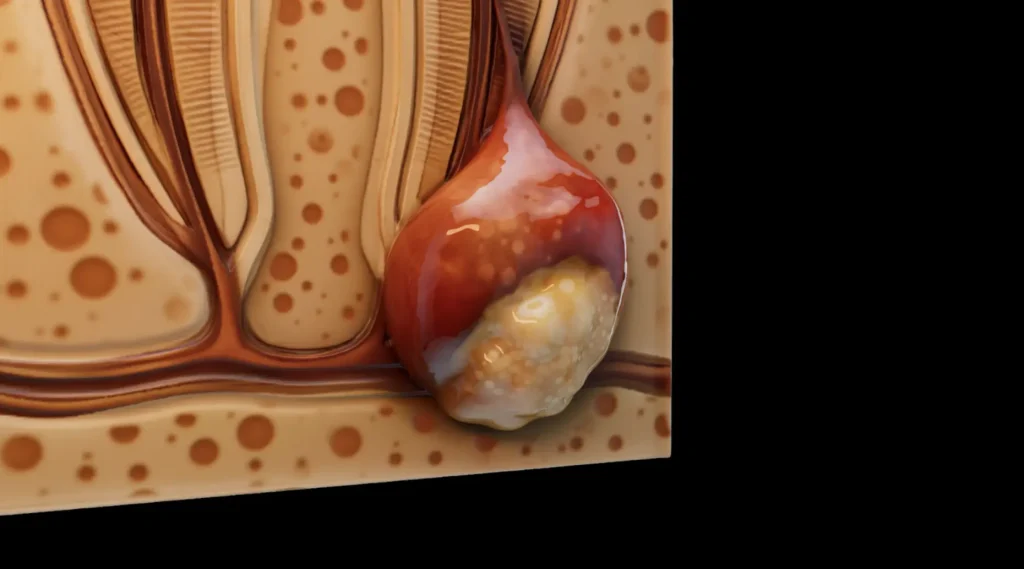

Zubni apsces je lokalizirana gnojna infekcija zuba i okolnih tkiva. Organizam se pritom pokušava obraniti ograničavanjem infekcije na jedno mjesto (stvaranjem gnojnog džepa), ali apsces ipak nije bezazlen.

Zubni apsces je gnojni džep koji nastaje uslijed infekcije zuba i okolnog tkiva.

- apsces koji nastaje unutar samog zuba (periapikalni apsces) i

- apsces koji se razvija u tkivu desni oko zuba (parodontalni apsces).